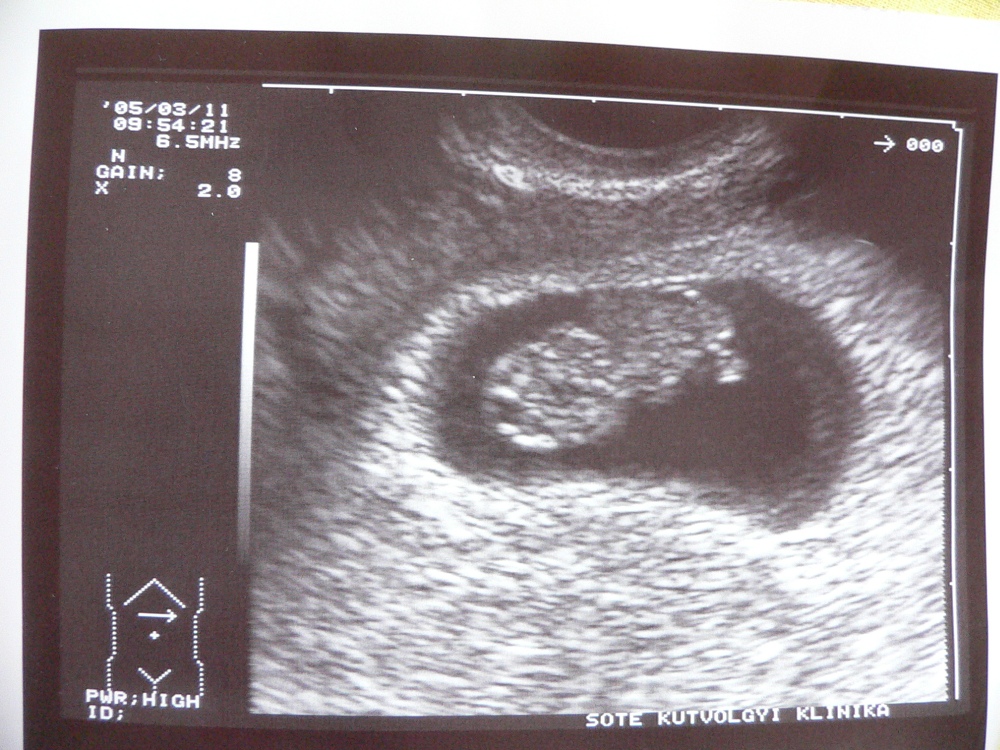

| 8. hetes ultrahang képe. egyértelműen kivehető a fej (bal oldal), aztán jobbra haladva a keze, alul a lába :-) |